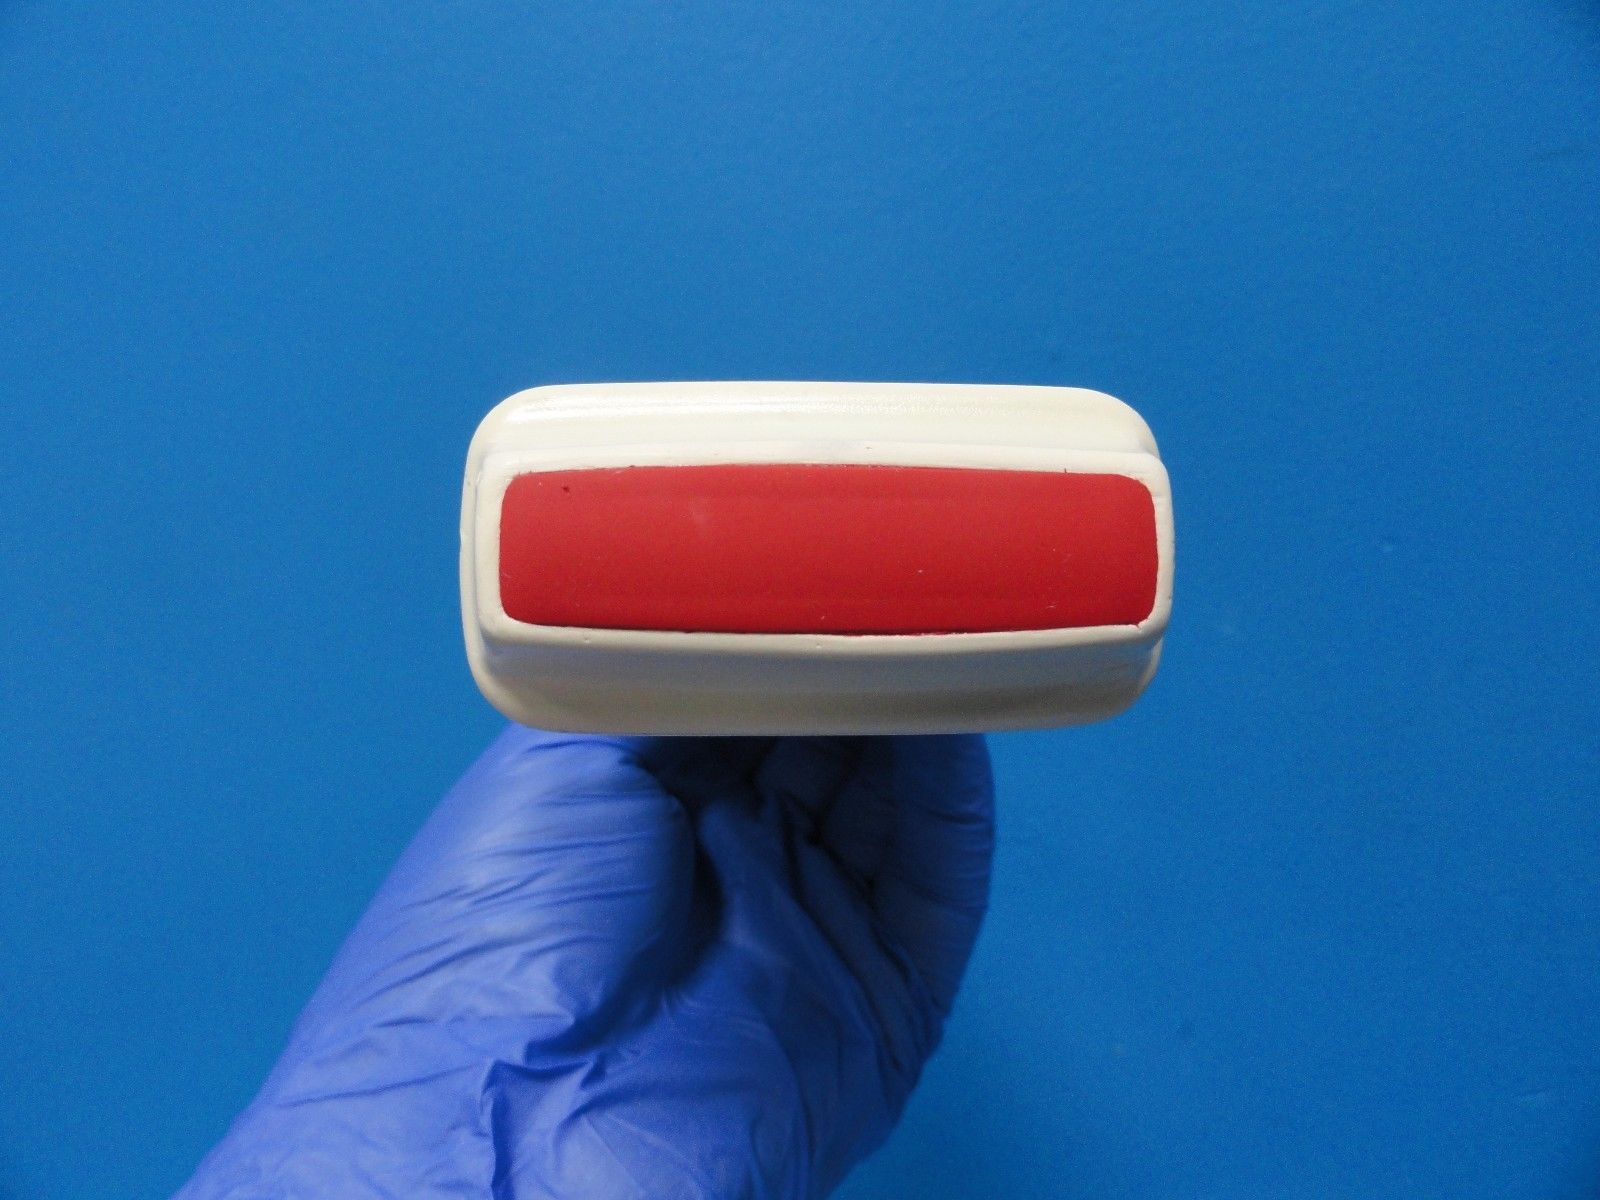

Philips S8-3 Ultrasound Transducer Probe

Sale price$ 14,387.70